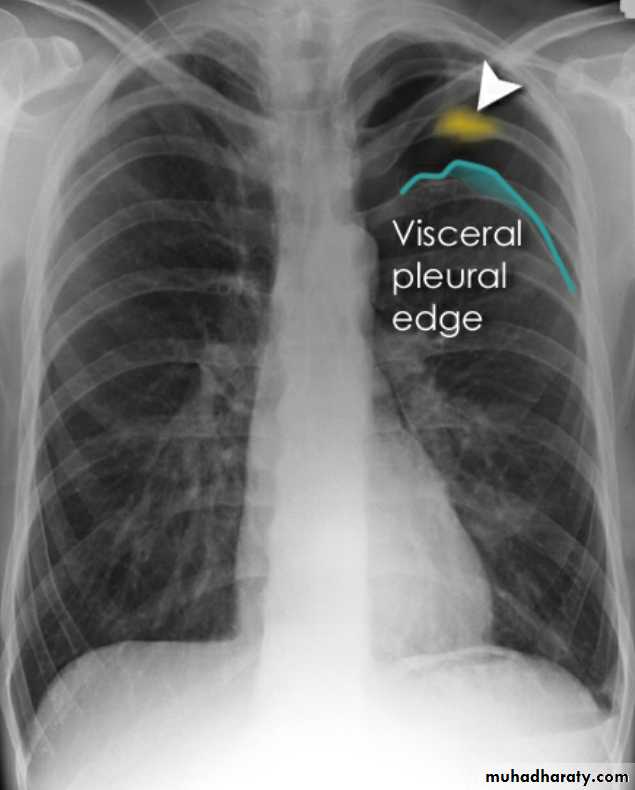

Pneumothorax

Pneumothorax refers to the presence of gas (air) in the pleural space. When this collection of gas is constantly enlarging with resulting compression of mediastinal structures it can be life-threatening and is known as a tension pneumothoraxIt is useful to divide pneumo thoraces into three categories :

Radiographic features

Chest radiograph

A pneumothorax is, when looked for, usually relatively easily appreciated. Typically they demonstrate:

visible visceral pleural edge see as a very thin, sharp white line

no lung markings are seen peripheral to this line

the peripheral space is radiolucent compared to adjacent lung

the lung may completely collapse

the mediastinum should not shift away from the pneumothorax unless a tension pneumothorax is present